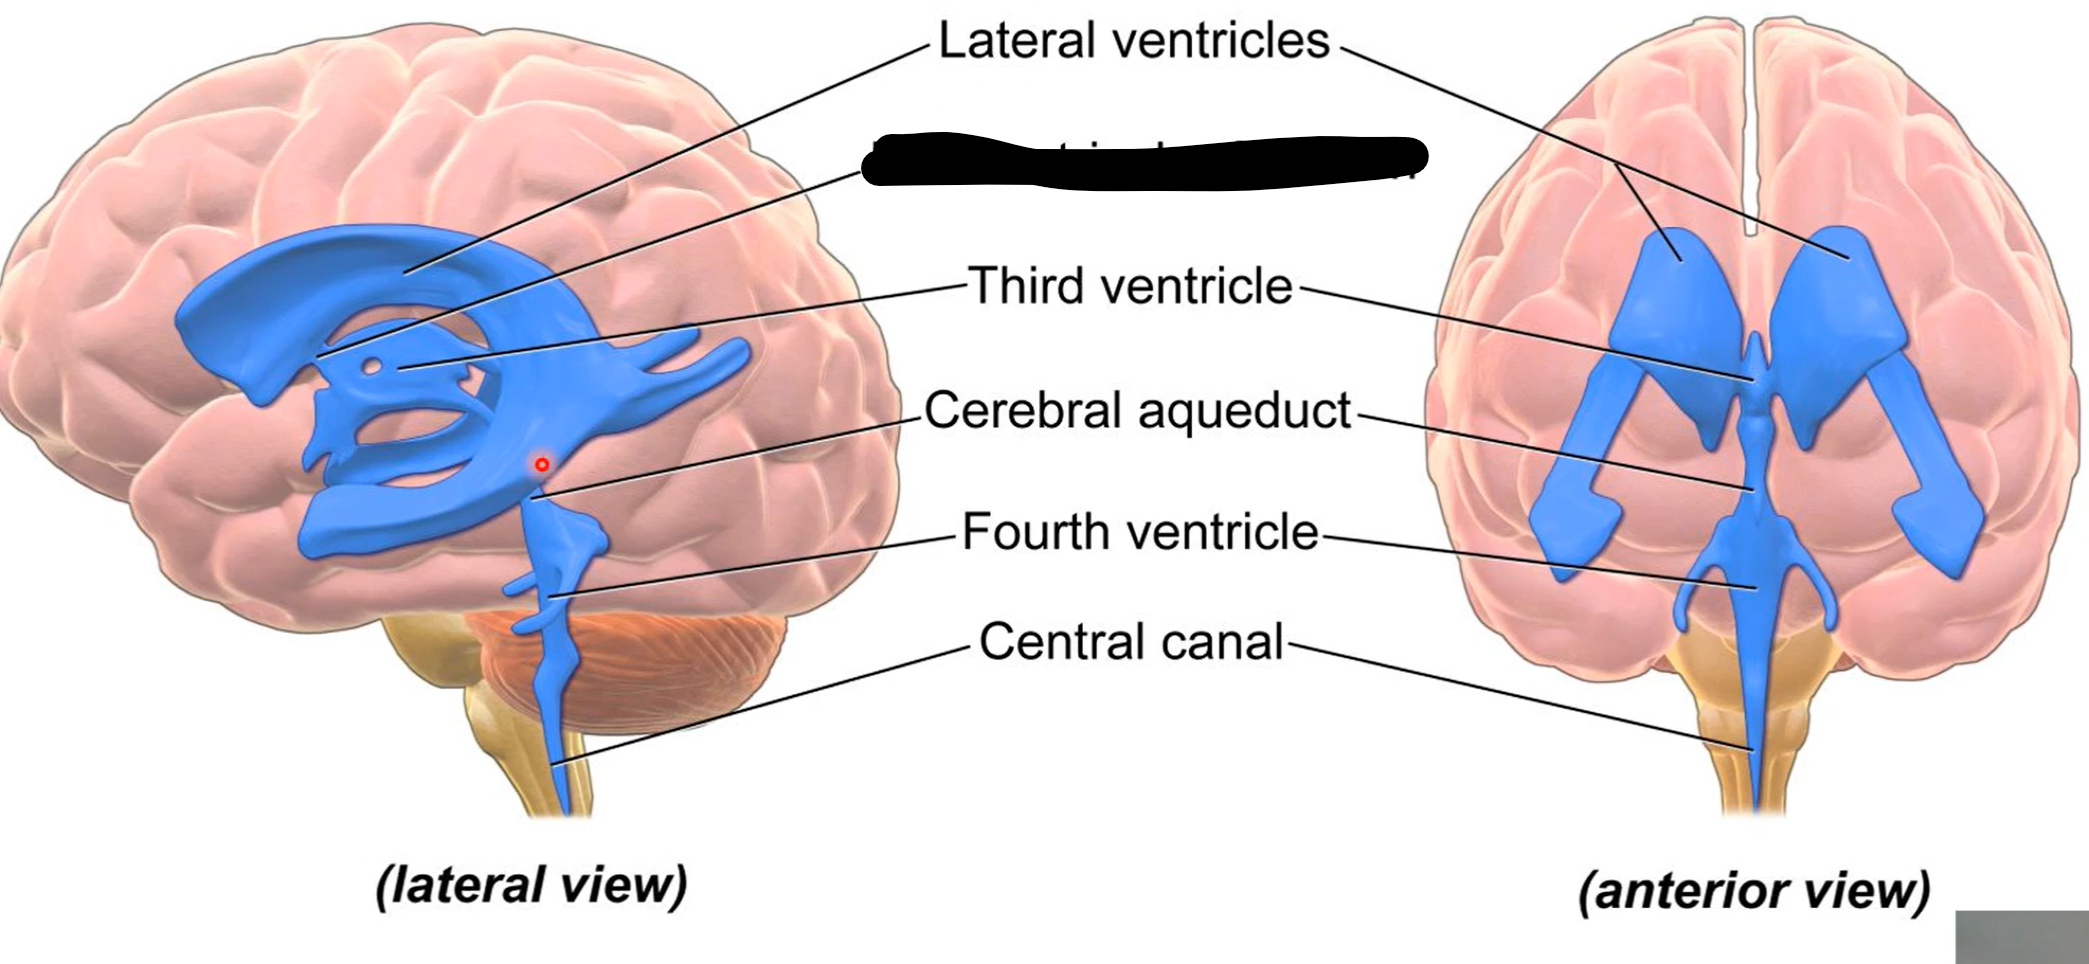

What do brain ventricles contain?

CSF

What makes CSF?

Choroid plexus

Where does CSF go from ventricles?

Subarachnoid space to enter circulation via arachnoid granulations

Choroid plexus

What carries CSF from 4th ventricle to subarachnoid space?

Median and lateral apertures

Arachnoid granulations

Lateral ventricles

Interventricular foramen

Third ventricle

Cerebral aqueduct

Fourth ventricle

Central canal